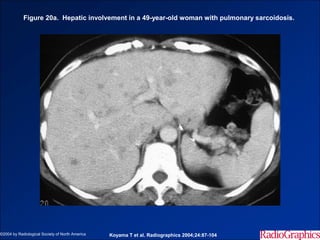

Hình ảnh trên CLVT

- Trước tiêm, nhiều ổ giảm tỷ trọng trong nhu mô gan và lách.

- Gan – lách to.

- Hạch ổ bụng.

- Sau tiêm, các ổ tổn thương đồng tỷ trọng với nhu mô gan.

Figure 20a. Hepatic involvement in a 49-year-old woman with pulmonary sarcoidosis.

©2004 by Radiological Society of North America   Koyama T et al. Radiographics 2004;24:87-104

• #54 Figure 20a.  Hepatic involvement in a 49-year-old woman with pulmonary sarcoidosis. (a) Contrast-enhanced abdominal CT scan shows multiple, irregularly shaped nodules of variable size in the liver. (b) T2-weighted MR image obtained after the administration of ferumoxides (Feridex; Advanced Magnetics, Cambridge, Mass) demonstrates multiple small, high-signal-intensity nodules throughout the liver.